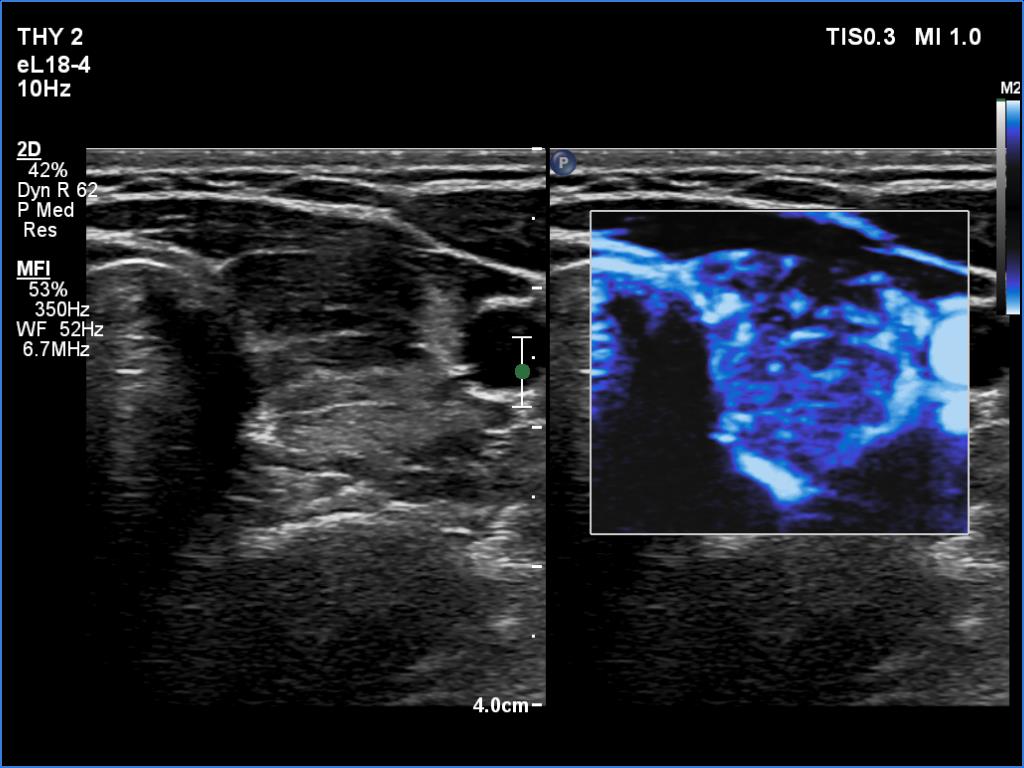

Right lobe, longitudinal scan

Left lobe, transverse scan, microflow imaging. The vascularity is increased.